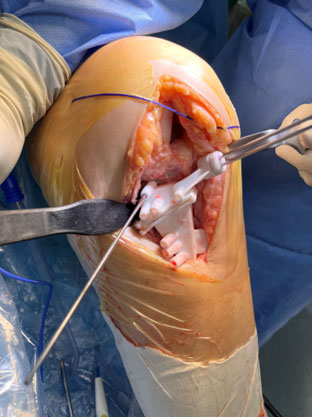

Positioning of the custom made cutting guide

Positioning of the custom-made cutting guide

Osteotomy